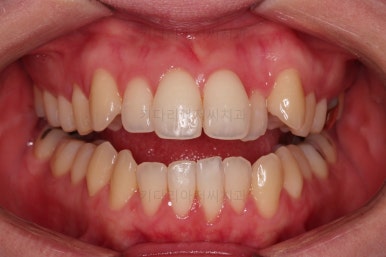

가지런하게 하는 것은 수월하기 때문에 이정도 모습까지는 6개월 이내로 걸리고요.

개방교합을 개선하면서 교합을 맞춰주고요.

디테일한 중앙선이라던지, 안에서 끄집어낸 치아의 각도라던지 비롯해서 환자분이 원하시는 느낌을 반영해서 마무리를 합니다.

1년 2개월이라는 비교적 짧은 기간안에 원하시는 부분을 깔끔하게 개선했습니다.